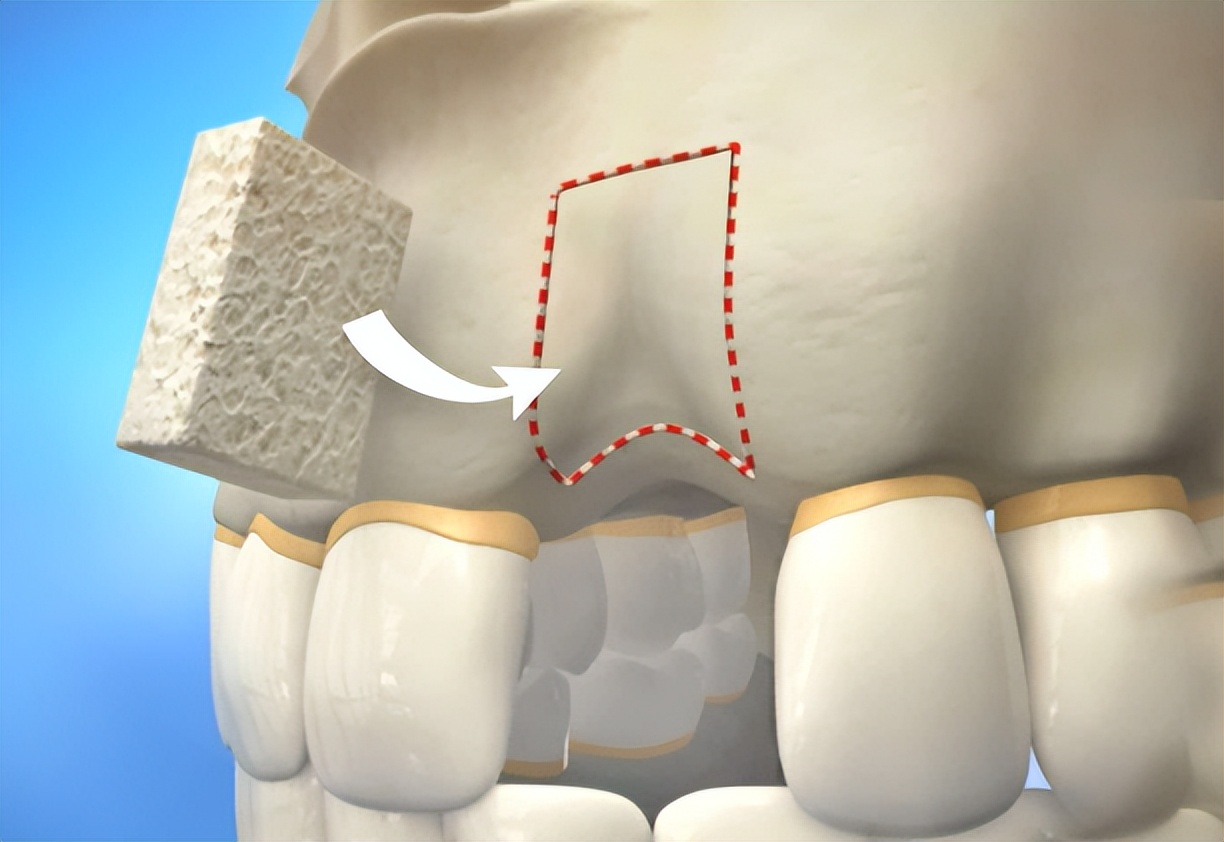

但可惜,很多缺牙久了的人,牙槽骨会萎缩,在CT片子上看,骨头薄得像薯片。这时就需要一种俗称“植骨”的技术。说的更简单点,就是盖房子前的土不够了,我得给你再填点。牙医会切开你的牙龈,撒点骨粉或者填充点人工蛋白海绵进去,再用可消融缝合线缝好。